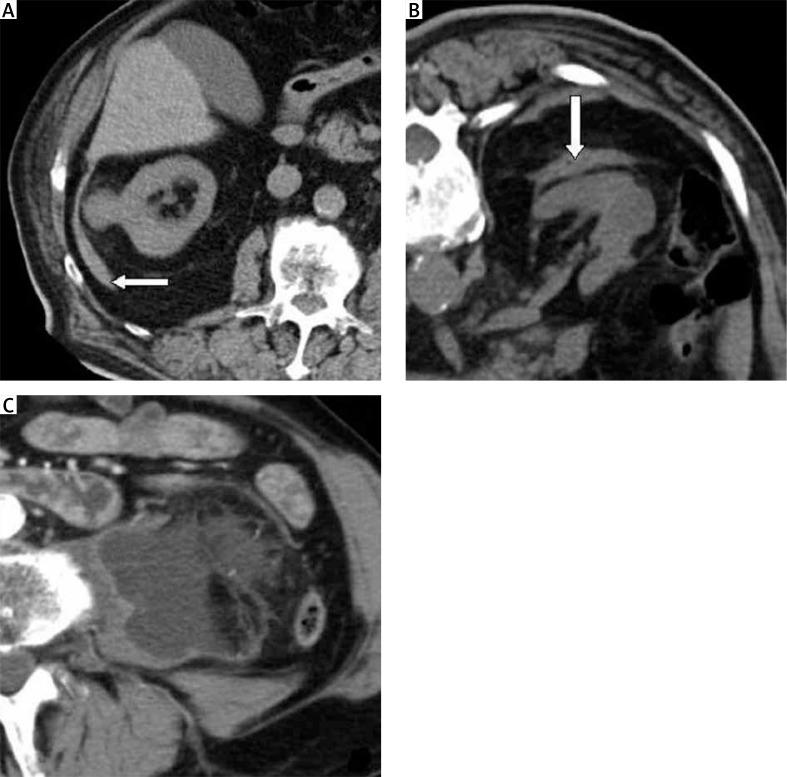

Over the course of 10 years, 91 ablation procedures in 64 patients for 68 tumors, of size 12-60 mm, were performed using only conscious sedation. These ablations were done under the guidance of computed tomography. We treated 41 males and 23 females with solitary kidney tumors (14 cases) and tumors in non-surgical candidates (54 cases).

In 50 (73.5%) tumors single treatment was successful; in 13 (19.1%) cases a second procedure was used successfully, and in the 5 largest tumors (sizes 45-60 mm, 7.4%) a third treatment was necessary. Within the follow-up 10 (15.6%) patients died, but none due to metastatic renal cell carcinoma. Only 1 serious complication was observed - retroperitoneal and psoatic hematoma. Early recurrence occurred in 18 (26.5%) tumors. Late recurrence was detected in 5 (7.4%) cases. In all cases complete local control of the renal tumors was reached.

在10年期间,对64例患者的68个大小为12 - 60毫米的肿瘤进行了91次消融手术,仅采用清醒镇静。这些消融手术在计算机断层扫描引导下进行。我们治疗了41例男性和23例女性,其中包括孤立肾肿瘤患者(14例)和不适合手术的肿瘤患者(54例)。

50个(73.5%)肿瘤单次治疗成功;13例(19.1%)患者成功进行了第二次手术,5个最大的肿瘤(大小为45 - 60毫米,占7.4%)需要进行第三次治疗。在随访期间,10例(15.6%)患者死亡,但均非死于转移性肾细胞癌。仅观察到1例严重并发症——腹膜后和腰大肌血肿。18个(26.5%)肿瘤发生早期复发。5例(7.4%)出现晚期复发。所有病例均实现了肾肿瘤的完全局部控制。